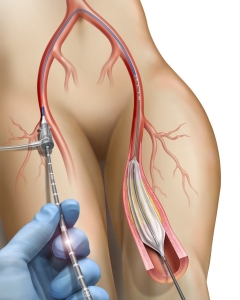

Internal Art Medical Illustration

Blending Art, Anatomy and Science for Creative Visuals

Patient & Professional Marketing

Welcome to my Patient and Professional Marketing page, where I harness the power of anatomical illustrations to educate and empower both patients and medical professionals. My unique approach combines artistry and education to convey complex surgical procedures and the utilization of medical devices in an easily understandable manner.